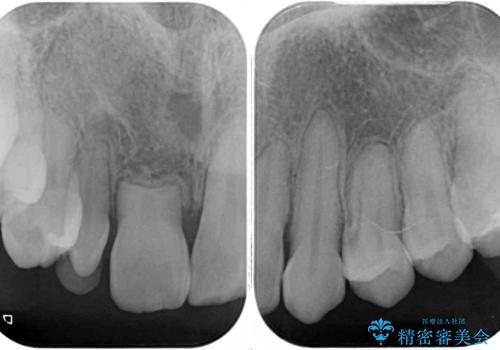

- 他院で矯正治療を終え、上顎前から2番目の歯の大きさを気にして来院された患者様です。

右側は小さく、左側は欠損により犬歯が前から2番に来ている状態でした。

矯正治療の段階で、矮小歯は前後にスペースが作ってあったため、極力左右対称の歯冠形態となるように補綴治療を行うこととしました。